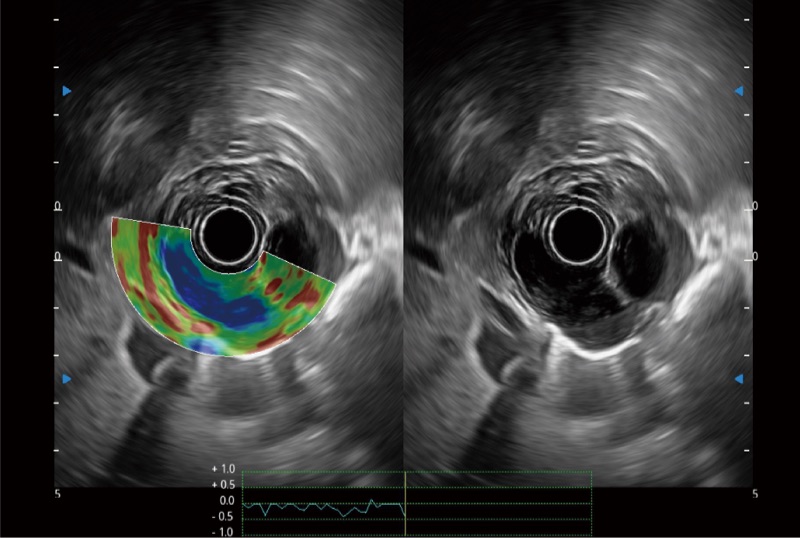

位移矫正技术

不可靠区域自动剔除

弹性定量分析软件

食管内间质瘤清晰显像